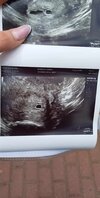

Byłam w poradni 'K'. Jest pecherzyk w macicy i krwiak. Pecherzyk 0,44cm . Ale mam w poniedziałek skierowanie do szpitala bo neta słabo rośnie i raczej nie ma szans na zdrowa ciaze w tym przypadku . Jutro znowu beta. Już wyglądam jakbym nie wiadomo co robila przez te siniaki na żyłach. Nie wi3m jak ja pójdę do szpitala jak mam w domu cycoholika..

Załączniki

• Messenger_creation_3c580714-130a-4d4f-8918-d21eccb721d2.jpeg

Messenger_creation_3c580714-130a-4d4f-8918-d21eccb721d2.jpeg

147,1 KB · Wyświetleń: 102